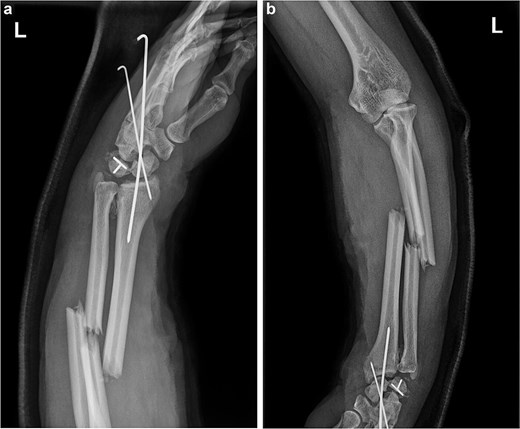

The forearm wound was closed after 1 week. After 2 weeks, the patient underwent surgery for carpal bone and ulnar radius fractures through a dorsal incision. The disarranged lunate, scaphoid, and triquetrum bones were realigned. Due to the incorrect fixation of the scaphoid and triquetrum fracture ends, the original Kirschner wires were removed, and a buried screw was used to refix the fracture end of the scaphoid bone. Kirschner wires and a locking plate were then used to restore the carpal alignment (Fig. 4). At the radial sigmoid notch site, small bone fragment was identified and fixed with a K-wire. Postoperative fluoroscopy revealed that the fracture ends were in good position, and the internal fixation was properly aligned (Fig. 5). After 6 months, the steel plate and Kirschner wires were removed from the wrist, and the patient gradually began functional exercises (Fig. 6).

(a and b) Anterior and lateral views of the wrist joint after 6-month follow-up.